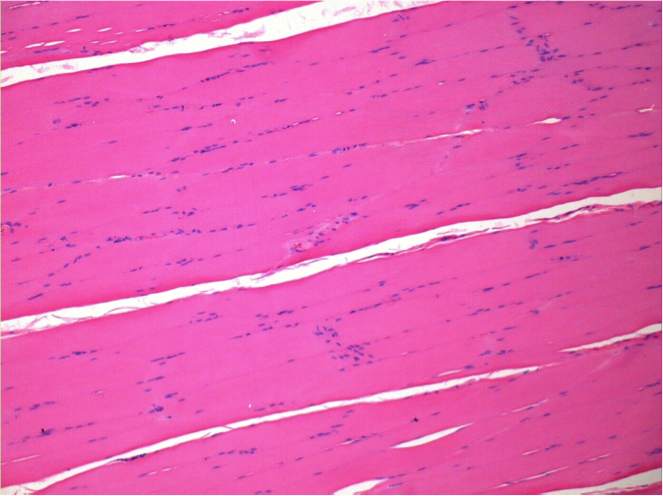

7 months (D210)after Endopeel IM Injection 0.1ml in the right pretibial muscle.

Complete Restitutio ad integrum after 7 months